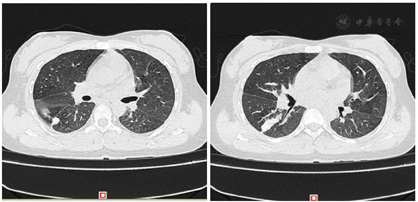

结合临床,该患者诊断为:(1)系统性红斑狼疮;(2)自身免疫性肝炎、肝功能不全;(3)全血细胞减少;(4)右中肺胸膜结节(性质待定)、右下肺结节钙化灶(性质待定)、右下肺少许炎症;(5)甲状腺功能减退。

患者转入我科后,进一步查骨髓细胞学及活检未见明显异常,尿培养阳性提示泌尿系感染,PPD皮试(2+),T-spot阳性,肺部CT有结节、钙化病灶(性质待定),怀疑有结核可能。给予抗感染、护肝降酶等治疗的同时,需积极排查结核,激素、免疫抑制剂治疗暂缓,给予血小板生成素(TPO)升血小板治疗,病情明确、感染控制后予足量激素抗SLE,患者病情好转出院。